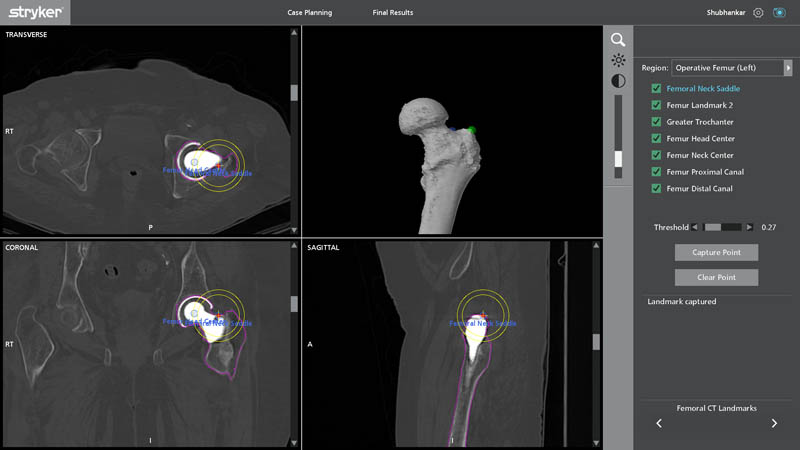

Femoral CT Landmarks

Segmentation is an advanced imaging and planning process where CT-based data is converted into highly detailed 3D anatomical models. This allows the surgeon to:

- Identify exact areas of bone loss

- Plan implant removal safely

- Customize implant size and placement

- Avoid vital structures

- Anticipate surgical challenges before entering the OT